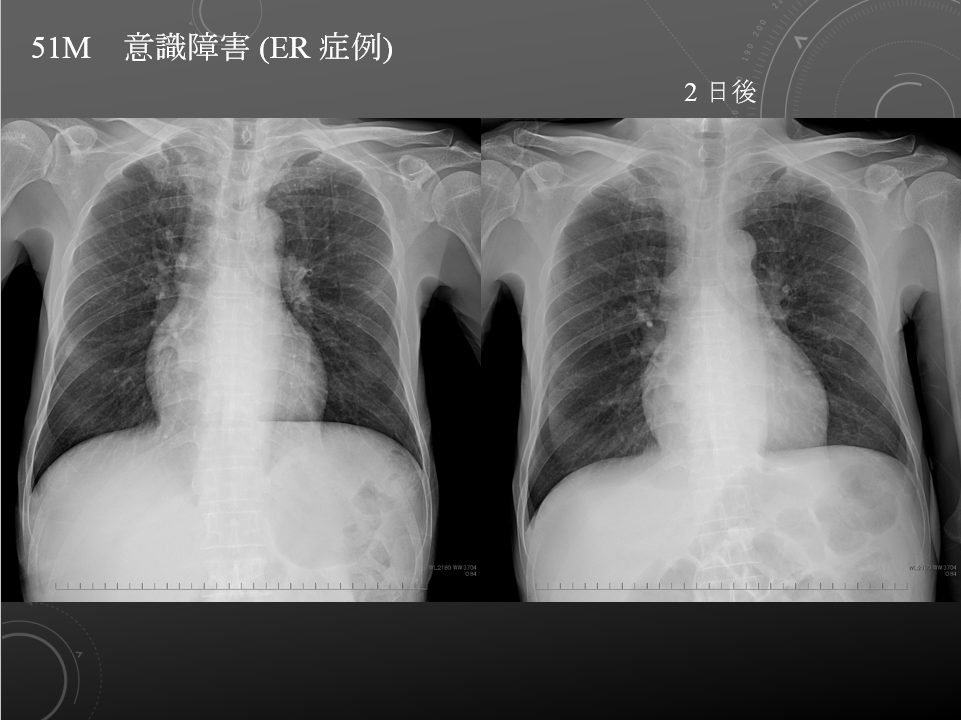

51M 意識障害 ER症例

胸部臥位単純写真

同日単純 CT を参照しています。

両肺野に異常陰影は指摘できません。

心縦隔陰影の拡大や胸水貯留所見は明らかではありません。

その他、特記すべき所見は認められません。

特記所見は認められません。

意識消失

51M 脳梗塞